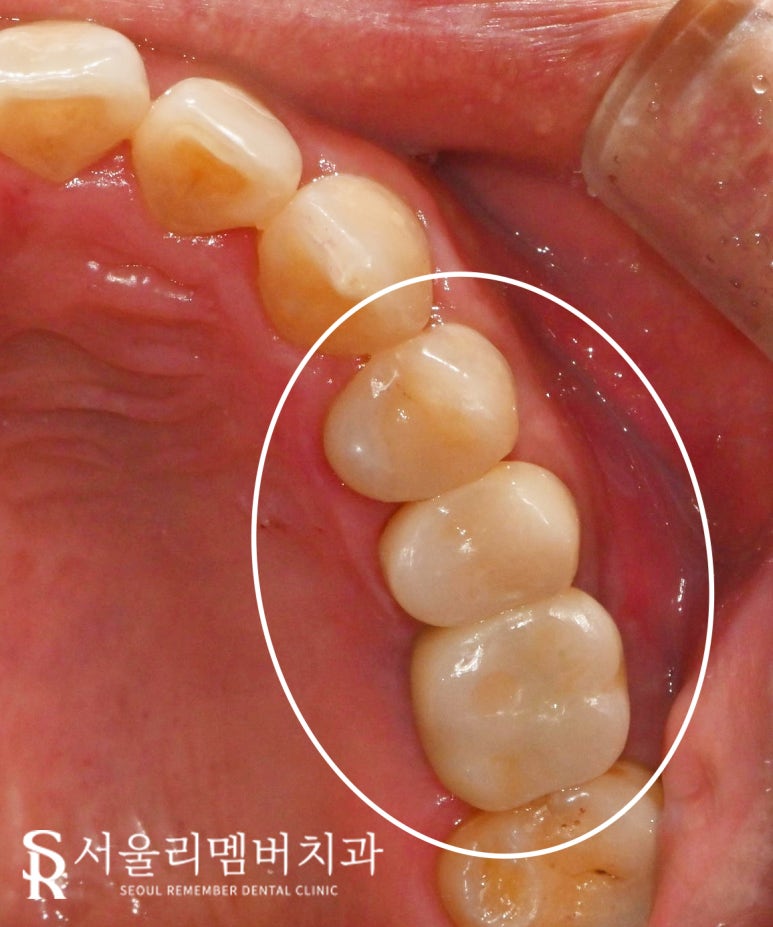

오늘 서울대입구 치과 케이스를 보면

첫 번째 작은 어금니(24번)부터

첫 번째 큰 어금니(26번)까지

약간의 파절이 존재합니다.

다행히 신경까지 손상되지는 않았지만,

많이 당황스러우셨을 것 같네요.

그런데 여기서 주의 깊게 살펴봐야 될 점은

단순히 24번 소구치에 존재하는

치관 파절이 아닌

바로 옆 25번에도 크랙이 발견되었다는 점입니다.

이 케이스도 비록 균열이 존재하긴 하나

크라운을 씌워 보호해두었으니

내 이를 조금이라도 더 쓰실 수 있을 겁니다.

뼈와 결합되는 기간까지 포함하면

몇 개월이 걸렸지만

잘 마무리가 되었습니다.